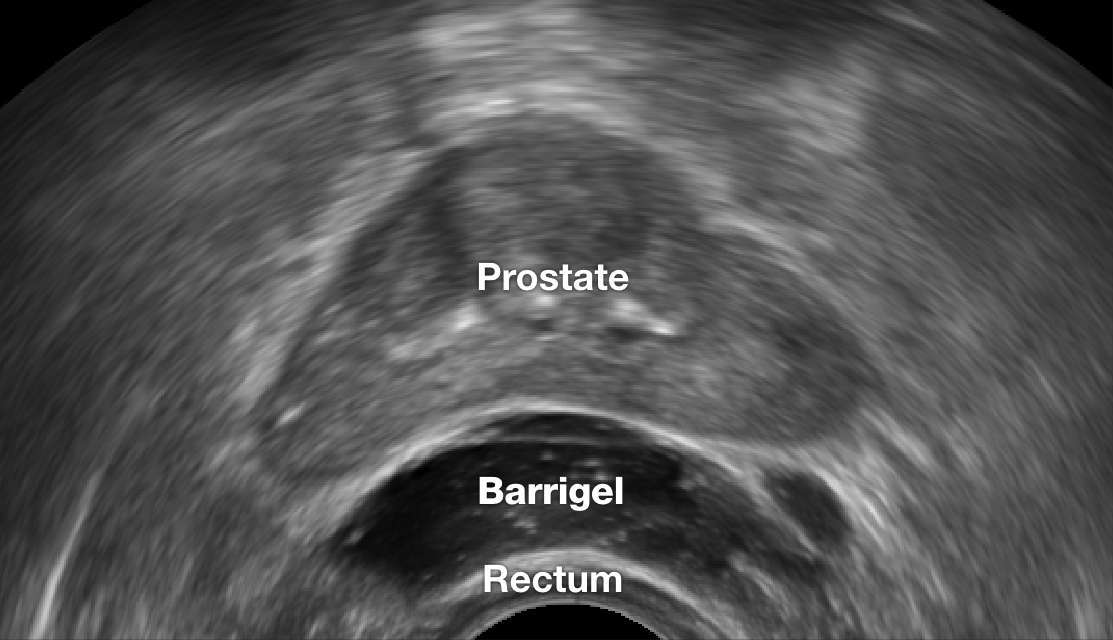

TRUS IMAGES

TRUS image courtesy of Neil F. Mariados, MD

Radiation Oncologist; New York, United States